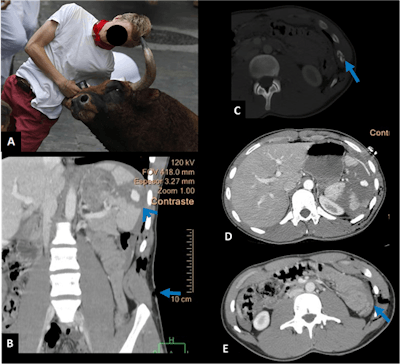

Goring can cause spectacular injuries, which can be undervalued at first sight.

"These injuries have an entry wound, but we don't necessarily know what happened inside the abdomen, and there can be different routes. CT is, of course, crucial in that setting," he said.

Miranda shared the case of a patient who presented with an injury caused by goring in his right rib. Looking at the images in detail, the radiologists noticed that the patient's right rib was pierced, and CT showed fracture on the 10th rib, in addition to mild pulmonary contusion.

"It's impressive how goring can generate such damage, with intestinal evisceration," said Miranda, highlighting the challenges of imaging such complex situations. "In that case, it was curious that the pneumoperitoneum wasn't due to the mechanical effect of goring entry, but rather to intestinal laceration, as surgery later confirmed."